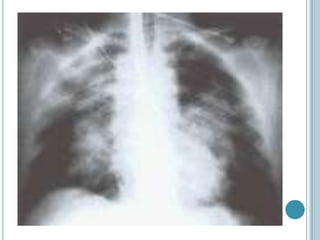

Fundamentalmente clínico. Debe basarse en la historia clínica y

confirmarse con radiografía de tórax.

Puede detectarlo antes de la aparición de signos clínicos.

Rx de Tórax, sin edema. Rx de Tórax, con edema.

DIAGNÓSTICO Fundamentalmente clínico. Debebasarse en la historia clínica y confirmarse con radiografía de tórax. Puede detectarlo antes de la aparición de signos clínicos. Rx de Tórax, sin edema. Rx de Tórax, con edema.